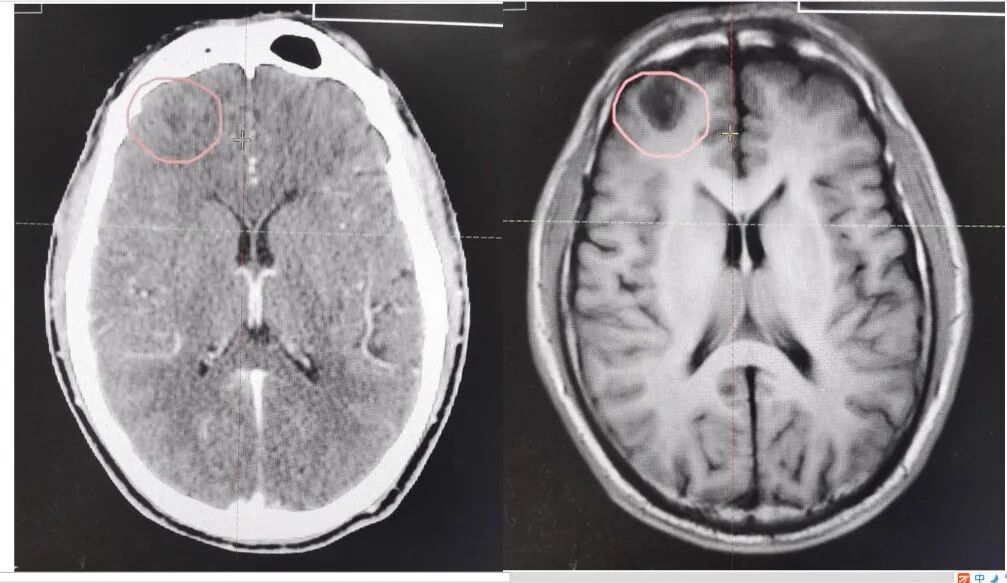

相比较CT图像技术,磁共振图像清晰度高,识别肿瘤更准确,特别是大脑等中枢神经系统以及腹盆腔等软组织区域,对肿瘤的诊治优势更显著:CT看不见的,磁共振能看见;CT上面看不清楚的,磁共振能看清楚(见下图);如颅脑、肝等器官内的肿块,肿瘤密度和周围正常组织的密度非常接近,在CT图像上面往往难以区分,就像几个坏人挤在好人堆里一样,大家穿的差不多的衣服,就很不好找到,这在磁共振图像(MRI)上就不是问题。又比如治疗儿童中枢神经系统的肿瘤,若肿瘤长在紧贴眼球或脑干的位置,我们打击(照射)肿瘤同时要保护眼球视神经要保护脑干,这就要非常清晰地知道肿瘤的边界。将磁共振技术应用于模拟定位,它可以准确找到肿瘤,指引加速器产生的高能射线进行打击。

CT图像(左)和磁共振图像(右)对比---左上角有肿瘤